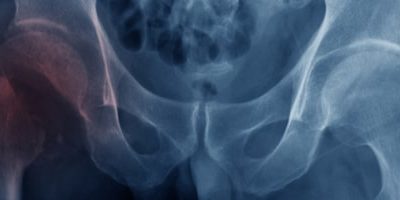

Одна из самых распространенных проблем пожилого возраста – остеопороз, возрастное заболевание, при котором костная ткань человека теряет свою прочность.